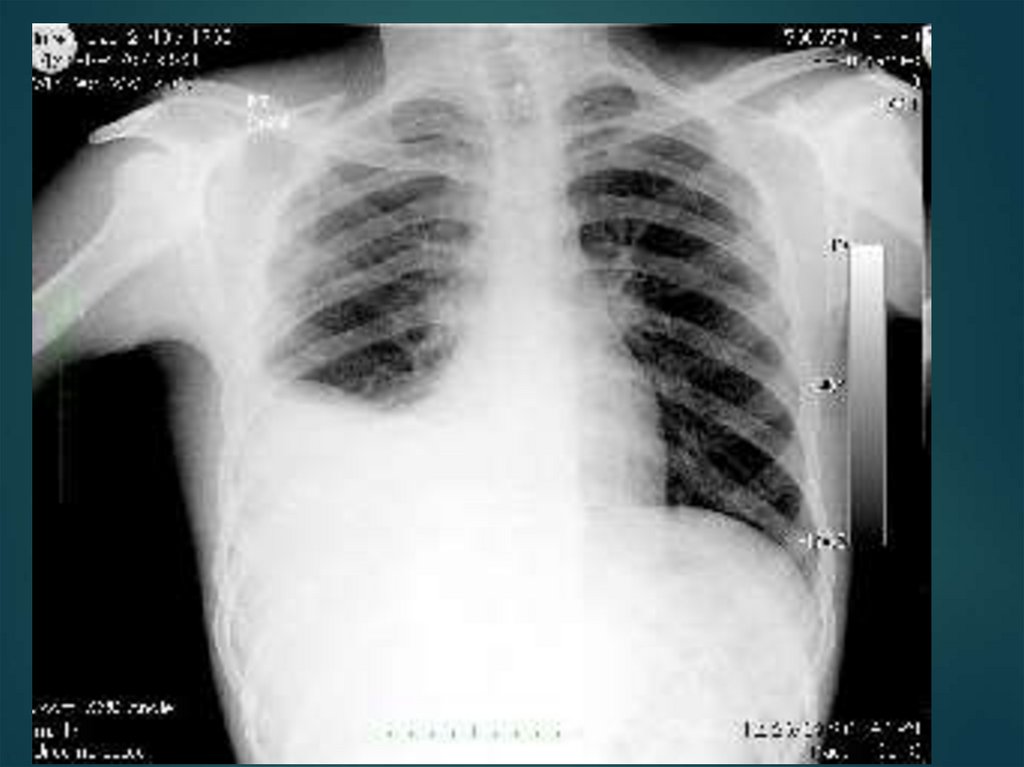

83.

84.

1 — участок плевральной

полости, заполненный

жидкостью

(притупленный или

тупой перкуторный

звук);

2 — линия Эллиса —

Дамуазо —

Соколова;

3 — треугольник

Гарленда

(тимпанический

перкуторный звук ателектаз);

4 — треугольник Грокко

— Раухфуса

(притупленный

перкуторный звук).